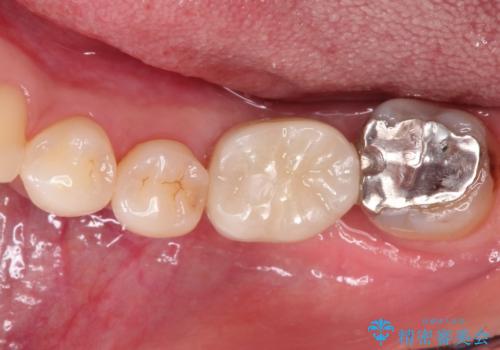

インプラントの種類:strauman SLActive

かぶせ物の種類:Bellezza screw retain